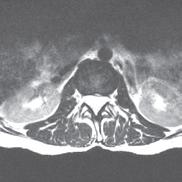

“One solution that we found is to use our Siemens MAGNETOM Free.Max 0.55T MRI Scanner,” says Dr. Seiberlich. As one of the few locations nationwide that owns and operates this “low field” machine, the MIITT team and UM Radiology have identified niche utilities, including the ability to conduct “in bore” biopsies--meaning the patient stays in the MRI scanner throughout the procedure. Now radiologists can clearly see the area that they want to biopsy, and accurately direct metallic needles without risk of damaging surrounding tissue. In addition to a wider bore, initially intended for larger patients or those with claustrophobia, the image quality of the scans is less affected by metal implants at low field strength. This is also advantageous when scanning patients with prior joint replacement surgery. “We can also capture MRI scans of parts of the body that are in motion, such as the heartbeat or blood flow,” she says. “Instead of a one second scan to make an image of a stationary body part, we can create a usable image in 20 milliseconds. We continue to discover special use cases that make this machine an exciting tool for us to have in radiology.”

One of the many benefits of utilizing the MRF method as opposed to traditional MRI techniques is that it can be applied across vendors and machines to enable quantitative comparisons. “Before MRF, the shades of gray you received depended on all sorts of factors,” says Tom Griesler, MS, third year BME PhD candidate, whose research interests include MRF sequence design and optimization for brain and abdominal imaging. Results varied based on the series, settings, and manufacturer. Using MR Fingerprinting, numerical physical parameters enable comparison across time and space.

“We’re also developing something called quantitative T1rho mapping, an MRI-based measurement technique for contrast-free myocardial fibrosis detection,” says Sydney Kaplan, MS, 4th year BME PhD candidate. “This is part of my research where we’re trying to avoid administering gadolinium based contrast agents to patients who may have kidney disease. With standard scanning technology, we can’t see fibrosis on an MRI image. However, by using T1rho or an alternative method, Magnetization Transfer (MT), both of which are sensitive to macromolecules like collagen or proteins, we can see subtle changes in heart tissue.”